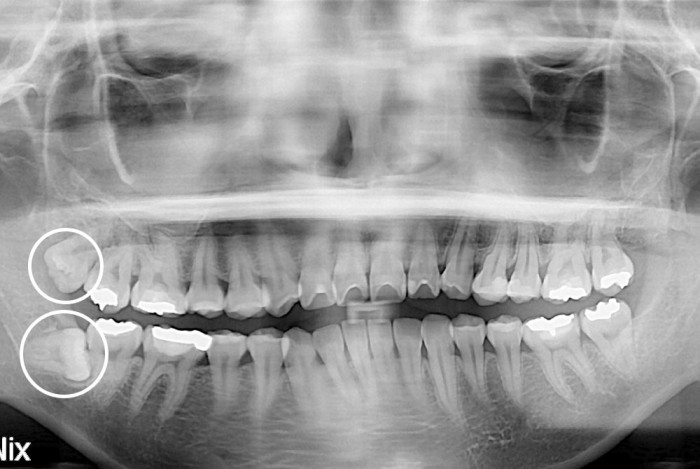

[사랑니] 사랑니

치료후 : 2019-10-23

세종치과는 구강악안면외과학 박사이신 원장님이 발치하는 치과입니다.